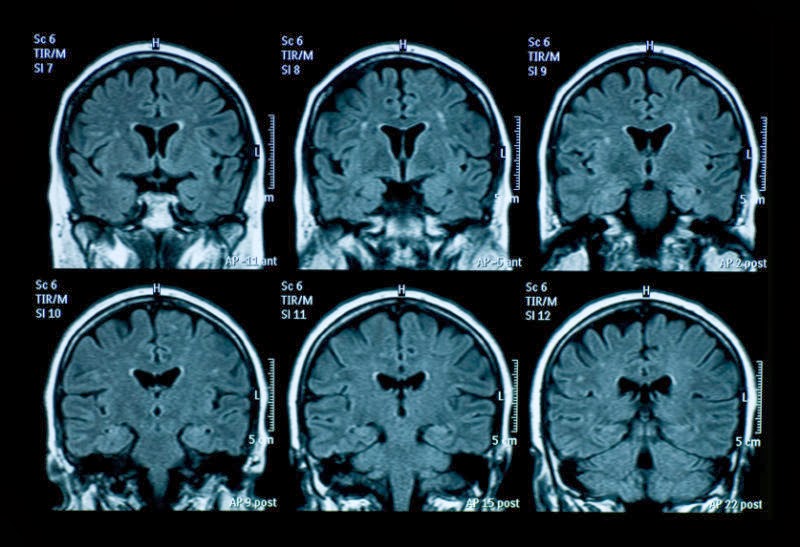

Cardiac (heart) imaging, breast imaging, brain, Magnetic Resonance Imaging (MRI) uses radio waves and a strong magnetic field to provide clear and detailed images of internal organs and tissues. MRI is different than other radiology procedures because it does not use radiation ... Doc Retrieval

MRI and Alzheimer's Disease Current and Future Uses of MRI in Alzheimer's Diagnosis. By Betsy Lee-Frye. Updated August 05, 2008 ... Read Article

Brain MRI may help narrowing the differential diagnosis, avoiding expensive genetic tests, or even establishing a final diagnosis. Since these disorders are caused by inherited enzymatic defects, concentrations of some metabolites may be abnormally low or high. ... Return Doc

Magnetic resonance imaging (MRI), formerly referred to as magnetic resonance tomography (MRT) or, in chemistry nuclear magnetic resonance (NMR), is a non-invasive method used to render images of the inside of an object. It is primarily used in medical imaging to demonstrate ... View Video